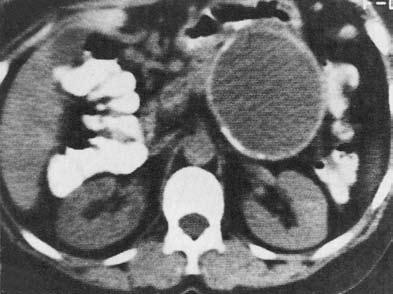

Ценным, хотя и более дорогим, методом диагностики панкреатических кист является КТ, дополняющая УЗИ (рис. 162, 163).

Оба этих метода помогают дифференцировать кистоподобные образования ПЖ от кистозного или опухолевого поражения других рядом расположенных органов, прежде всего почек и надпочечников. Под контролем УЗИ или КТ осуществляется и диагностическая пункция кист через переднюю брюшную стенку для исследования их содержимого (биохимический анализ, в том числе на ферменты ПЖ, цитологическое исследование осадка, микробиологическое исследование).

Рис. 162. Ультразвуковое исследование. Псевдокиста поджелудочной железы

Рис. 163. Компьютерная томография. Псевдокиста поджелудочной железы